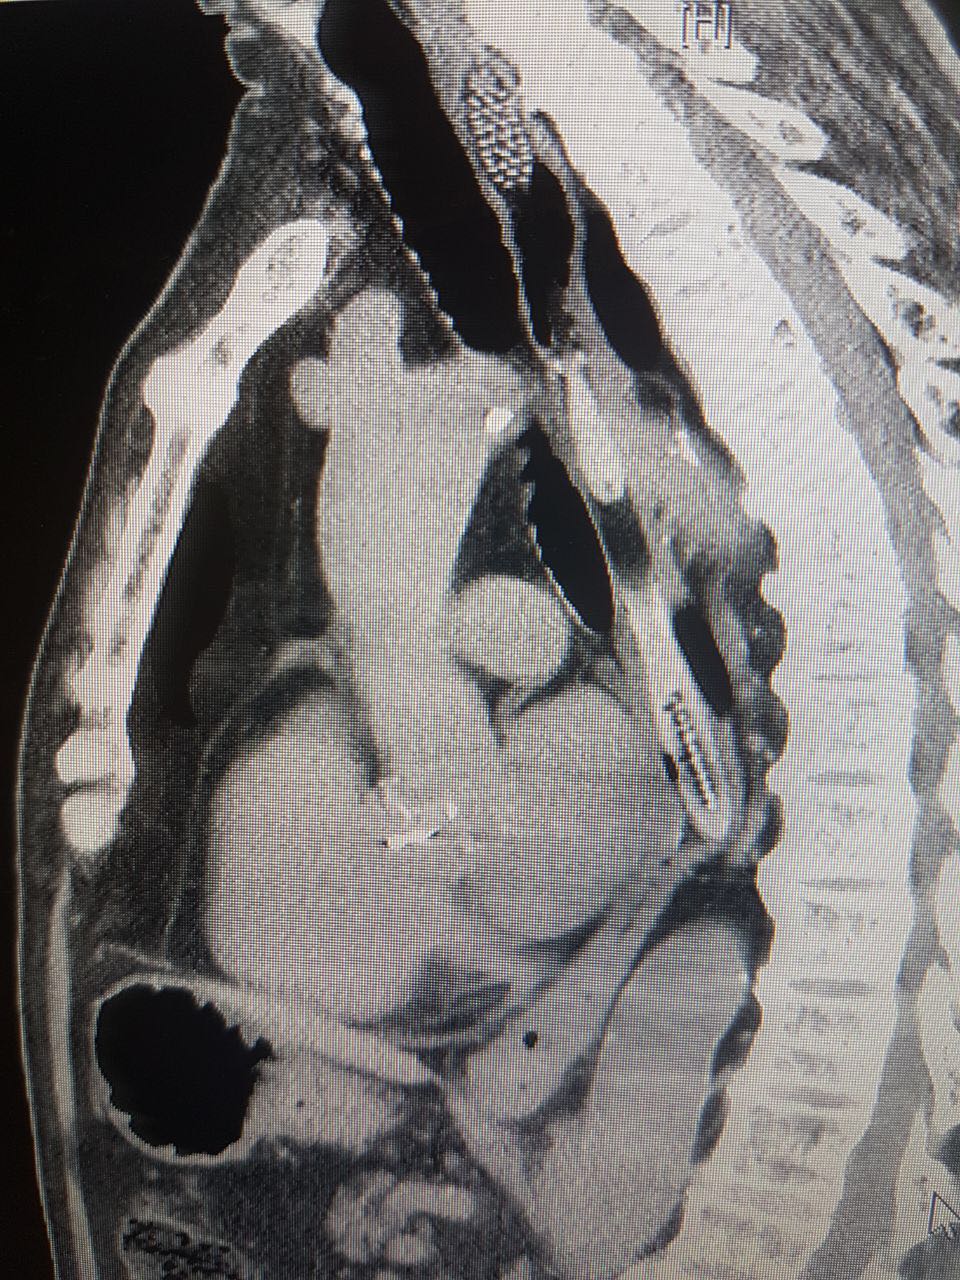

ד"ר רונית בר חיים, ממחלקה כירורגיה ב' שטיפלה בו בחדר המיון, הורתה על ביצוע בדיקת סי. טי. דחופה, בה ניתן היה להבחין בגוף זר שהתברר כמברשת השיניים, כשהיא תקועה בתוך לועו של הקשיש ולא ניתן היה להבחין בה עד לביצוע פעולות דימות.

תוך זמן קצר הועבר הקשיש לחדר ניתוח שם המתינו לו ד"ר אוהד רונן וד"ר אילי ליוס ממחלקת א.א.ג. ניתוחי ראש וצוואר במרכז הרפואי לגליל, שביצעו פעולה ניתוחית מהירה במהלכה נשלפה מברשת השיניים ללא שגרמה לנזקים או לסיבוכים במצבו הרפואי של הקשיש, שנותר להשגחה במחלקה ולאחריה שוחרר לביתו.